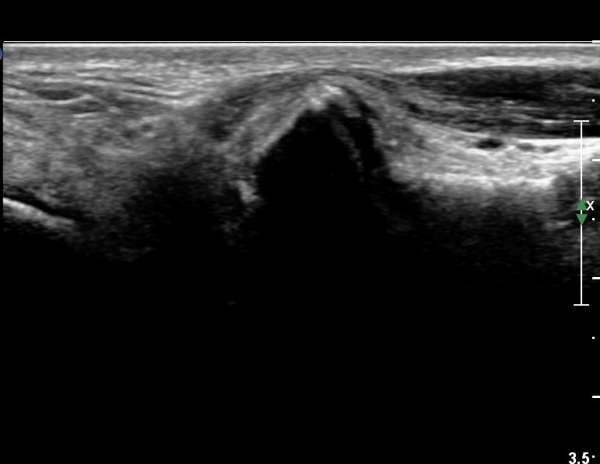

¹ß¸ñ °üÀý Á¾´Ü¸é°Ë»ç¿¡¼­ °æ¹ÌÇÑ °üÀý³» ºÎÁ¾À» º¸ÀÓ(»çÁø 1).

Sinus tarsi Á¾´Ü¸é, Ⱦ´Ü¸é°Ë»ç¿¡¼­ sinus tarsi ³» ºÎÁ¾À» º¸ÀÓ(»çÁø 5, 6).